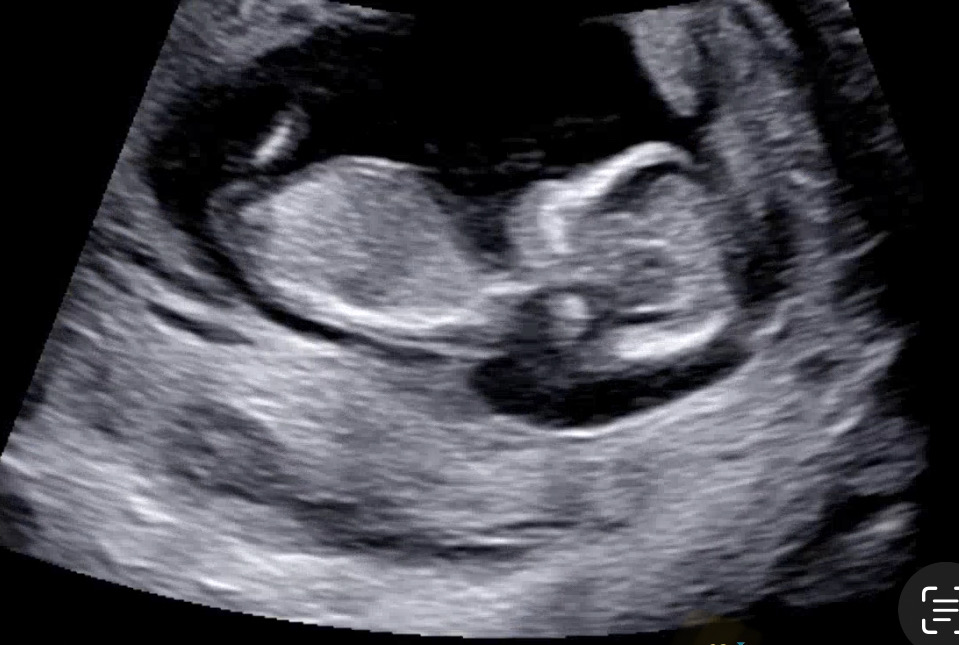

11주 6일차 각도법 봐주세요~~~

11주 6일차에 병원 다녀왔는데, 뭐가 보이시나요.. 각도법 해보려고 공부했는데 막상 초음파 보니까 안보이네요😂 의견 부탁드려요!